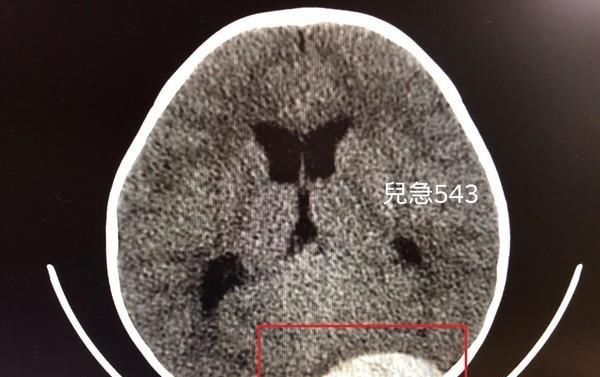

红色框框处为男童脑部出血位置。(图/吴昌腾医师授权提供)

提及硬脑膜上出血的危险性,吴昌腾指出,该伤害会引起「动脉破裂出血」最常见的是中脑膜动脉破裂,因为动脉出血,因此症状可能快速恶化。可从男童的电脑断层影像中看见「纺锤状的白色区块」,即为出血位置,所幸经过手术治疗后,目前还在复健中。